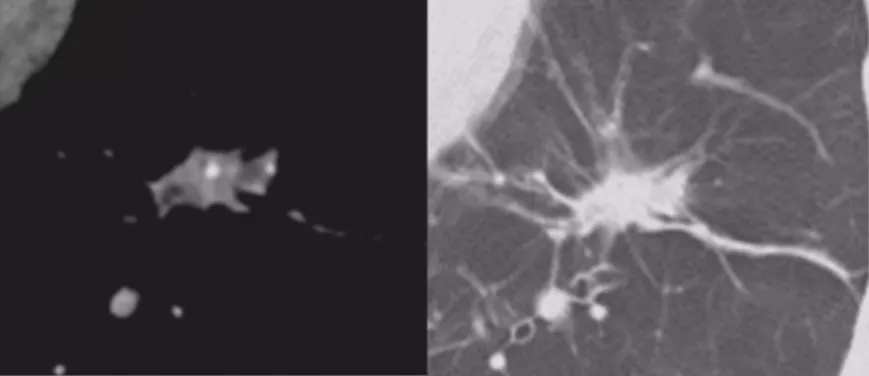

毛刺征

短毛刺(左)长毛刺(右)

毛刺又分长毛刺和短毛刺,短毛刺为肿瘤细胞向邻近肺实浸润时,支气管血管鞘或局部淋巴管阻挡,或肿瘤的促结缔组织生成反应的纤维带,其预测恶性的阳性预测值88%-94%。长毛刺是炎性的表现,良性病变边缘亦可见毛刺,多较长、柔软,常由增生的纤维结缔组织所形成,如炎性假瘤和结核球的毛刺为纤维包膜外增厚的小叶间隔。但是长度多少叫做长毛刺,多短叫短毛刺,没有明确定论,但是总体来说毛刺还是有一定规律的。